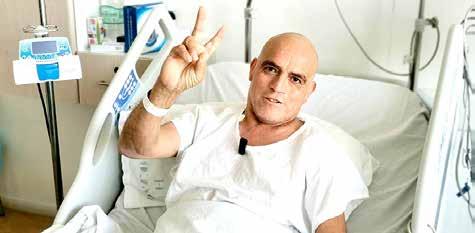

FAMILIA BUSCA RECURSOS. Ignacio, quien vive en Curicó, sufre una extraña enfermedad, la cual requiere de un medicamento que solo se obtiene en el extranjero.

FAMILIA BUSCA RECURSOS. Ignacio, quien vive en Curicó, sufre una extraña enfermedad, la cual requiere de un medicamento que solo se obtiene en el extranjero.

Padecimiento. Sufre una extraña enfermedad, la cual requiere de un medicamento que solo se obtiene en el extranjero.

CURICÓ. A las pocas semanas de vida, el pequeño Ignacio Muñoz (actualmente de dos meses y medio) fue diagnosticado con atrofia muscular espinal tipo 1, que es la más severa de todas.

Su padre, Joaquín Muñoz, explicó que el 25 de octubre le entregaron los resultados que dieron cuenta de la situación de salud de su hijo.

“Ignacio nació bien y fuimos a un control sano de rutina del mes y la doctora nos alarmó y nos dijo que no estaba muy bien. No se movía, estaba flojito y no levantaba ni movía sus bracitos ni piernas”, recordó.

En contacto con diario La Prensa, aseguró que el golpe fue duro, pero que están haciendo todos los esfuerzos para revertir la situación.

“El miércoles 16 de noviembre se empieza un tratamiento en el Hospital Luis Calvo Mackenna con el medicamento spinraza, es un estudio científico, en verdad”, contó.

Sin embargo, la esperanza está centrada en obtener el remedio zolgensma, cuyo valor su-

Se habilitaron varias cuentas bancarias para hacer los aportes.

pera los mil 900 millones de pesos (repara el gen defectuoso, deteniendo la enfermedad y solo se obtiene en el extranjero).

Joaquín Muñoz explicó que ese medicamento “se administra solo una vez en la vida, vía

intravenosa, y se han obtenido buenos resultados en los niños a los que se les ha aplicado”.

Hace alrededor de una semana, los padres de “Nachito” comenzaron una campaña soli-

daria para reunir el dinero para el remedio más caro del mundo.

Su madre, Camila Martínez, se mostró sorprendida con el apoyo obtenido en las redes sociales. “Hemos recibido una cantidad de ayuda impresionante, somos harta gente la que está manejando las redes y así y todo no damos mucho abasto con los mensajes”, sostuvo.

Agregó que se han organizado cicletadas, campeonatos de

pádel, de fútbol, una rifa, entre otras actividades.

Esta joven madre señaló que han golpeado muchas puertas y que se han reunido con varias autoridades como el alcalde de Curicó, la gobernadora regional, el delegado presidencial provincial, entre otros.

“Nos estamos moviendo por todos lados y la idea es que esto llegue al Presidente, porque hoy día no solo el Ignacio está en esta situación, hay más niños en el país, y ninguna fami-

lia tiene mil 900 millones para costear el medicamento”, acotó. Su padre puntualizó que hay que crear conciencia de esta enfermedad y visibilizar este tipo de enfermedad. “Ojalá que este tipo de males raros los puedan financiar el Estado”, indicó. Además, se habilitaron algunas cuentas bancarias para que la gente pueda ayudar.

Si usted quiere saber más de esta historia puede entrar a Instagram a la cuenta @juntosxnachito.